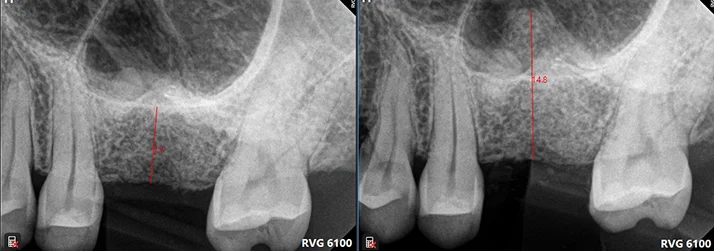

Maxillary Sinus Lifting in Mill Creek WA

Maxillary sinuses are located above the upper premolars and molars. It is a cavity separated from the alveolar bone by a layer of sinus membrane. After the teeth extraction, the width and height of the alveolar bone decrease with time. The sinus membrane also expands downward to cause insufficient bone of the implant area. At this time, it is necessary to evaluate the feasibility of sinus lifting surgery. The floor of sinus will be lifted and an extra space will be created for bone filling to increase the volume of bone to support the dental implant.